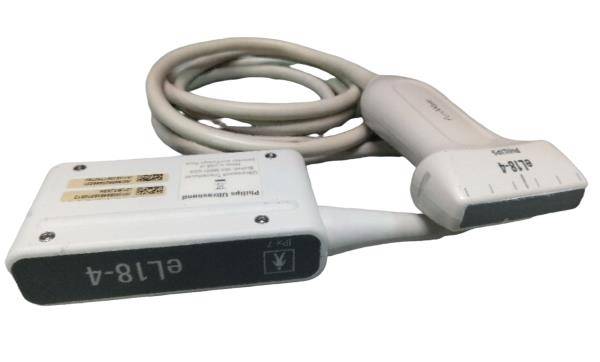

This state-of-the-art machine comes with two probes, ensuring versatility for different diagnostic needs. The SIUI Apogee 2300 supports DICOM (Digital Imaging and Communications in Medicine) which allows seamless integration with hospital information systems and ensures efficient workflow and storage management. The portability of this machine does not compromise its performance, as it delivers crystal-clear images that are critical for precise diagnostics.

In addition to its technical features, the Portable OB/GYN Ultrasound Machine is also designed with patient comfort in mind. The smooth operation and efficient scanning reduce the need for lengthy or repeated procedures, minimizing discomfort and improving patient experience. The two included probes offer flexibility in imaging, allowing for both abdominal and transvaginal examinations with ease.